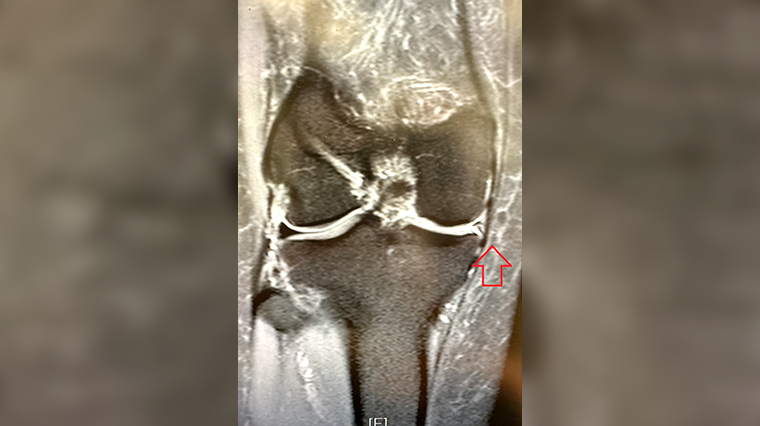

▲手術前,核磁造影檢查發現半月軟骨不見蹤跡。(圖/台北慈濟醫院提供)

一般而言,醫師可透過病人主訴、理學檢查以及核磁造影確認患處情形,治療方式通常根據受傷的型態、位置、嚴重程度來選擇。若破裂情形尚可修復,可運用縫合方式,保留半月軟骨的完整結構;若無法修復,則可利用關節鏡,將鬆動、碎裂嚴重的半月軟骨碎片清除,避免碎片卡在關節間導致腫脹發炎;若是半月軟骨有明顯缺失或已經近乎全部切除,異體移植為最佳選擇,目前仍以骨骼捐贈者的半月軟骨為主。